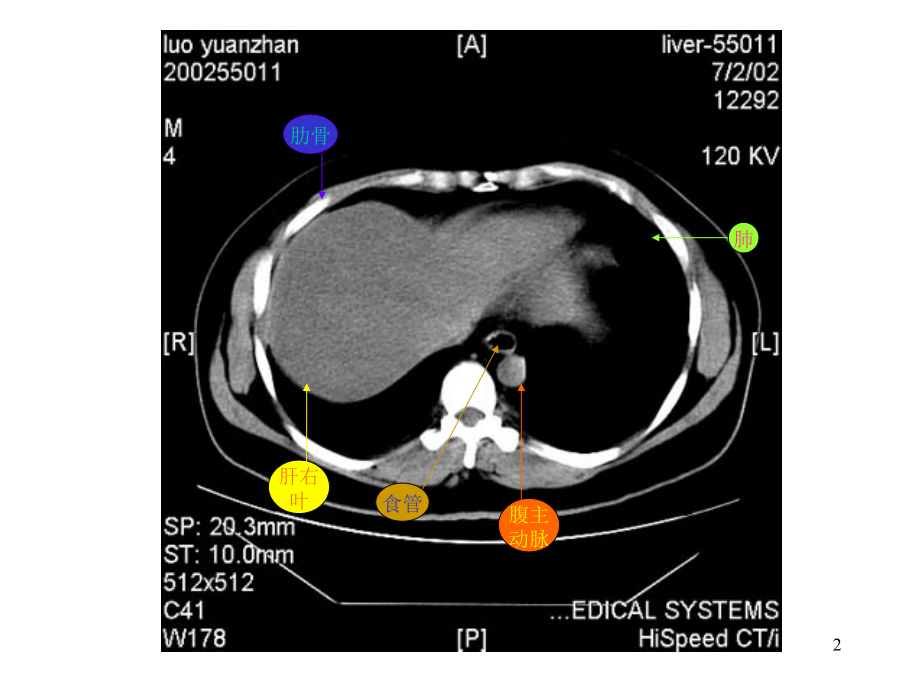

单击此处编辑母版标题样式,单击此处编辑母版文本样式,第二级,第三级,第四级,第五级,*,肝右,叶,横膈,肺,胸椎,脊,髓,腹主,动脉,食管,肋骨,1,肋骨,肝右,叶,腹主,动脉,食管,肺,2,肝左,叶,肝右,叶,腹主,动脉,胃,脾,肝尾,叶,3,肝右,叶,尾叶,膈脚,脾,门静,脉,肝左,叶,胃,4,肝右,叶,膈脚,腹主,动脉,脾,胆囊,胃,5,肝右,叶,下腔,静脉,胰腺,脾,胃,腹主,动脉,6,肝,右叶,心脏,腹主,动脉,下腔,静脉,脊髓,食管,肺,7,肝左,叶,肝右,叶,腹主,动脉,下腔,静脉,胃,脾,脊髓,8,肝左叶及,肝左动脉,肝右叶及,肝右动脉,腹主,动脉,下腔,静脉,胃,脾,肝尾,叶,9,肝右,叶,下腔,静脉,腹主,动脉,胃,脾,膈脚,10,肝静,脉,下腔,静脉,腹主,动脉,食道,肝右叶,11,下腔,静脉,肝右,叶,肝静,脉,肝左,叶,腹主,动脉,胃,脾,肝尾,叶,12,肝右,叶,下腔,静脉,腹主,动脉,门静脉,主干,肝左,叶,胃,脾,13,肝右,叶,下腔,静脉,门静,脉,腹主,动脉,膈脚,脾,胃,14,肝血管瘤CT平扫呈低密度灶,,密度均匀,边缘较清。,肝血,管瘤,15,静脉注入造影剂后CT扫描,动脉期示:病,灶由边缘向中心结节状强化,逐渐填满,其密度,与同层腹主动脉相似。,腹主,动脉,肾,肝血,管瘤,16,静脉期示病灶进一步强化填充,呈密度,较均的高密度灶,显示更清楚。,肝血,管瘤,17,2分钟后,平衡期CT扫描示病灶仍呈较高,密度,显示清楚,表现为“早出晚归”征,肝血,管瘤,18,CT平扫示肝脏左右叶普遍增大。,19,静脉注入造影剂后CT扫描,,静脉期示肝实质,呈不均匀强化。,门静,脉,20,肝硬化:CT平扫示肝脏,左右叶体积缩小,边缘,欠平整,肝裂增宽,肝裂,增宽,21,肝硬化并门静脉高压,,静脉注入造影剂后,静脉期CT扫描示:脾门静脉曲张。,脾门静,脉曲张,脾,肝右,叶,肝左,叶,22,肝癌CT平扫示:肝脏体积明显增大,边缘,不平整,肝实质密度不均,内见结节状、,团块状低密度癌灶,边缘模糊,密度不均。,肝右叶,巨大癌灶,肝内结,节状癌灶,23,静脉注入造影剂后CT扫描,动脉期示:肝内,癌灶不均匀增强,密度增高,其内见肿瘤,坏死部分不强化,呈更低密度。,癌灶增强,,密度增高,瘤内坏,死部分,呈更低,密度,静脉,早显,肿瘤,血管,肿瘤,假包膜,24,静脉注入造影剂后CT扫描,静脉期,示下腔静脉内癌栓呈低密度充盈缺损表现,。,肝右叶,癌灶,腹主,动脉,25,静脉注入造影剂后CT扫描,静脉期示:由于,造影剂洗脱,肿瘤呈较低密度。本例见癌肿,侵犯门静脉,门脉左支受压变形,门脉右支,未见显影。,门静脉左,支受压变形,肝内,癌灶,26,静脉注入造影剂后CT扫描,平衡期示:肝内癌,灶随造影剂进一步洗脱呈低密度表现。本例,门静脉左支内还可见稍低密度癌栓。,门静脉左支,及其内癌栓,肝内,癌灶,27,胆囊体积缩小,,胆囊壁稍厚。,肾,胰,肝,肾,静脉,腹主动脉,28,慢性胆囊炎CT平扫示:胆囊体积缩小,,胆囊后壁见一类椭圆形高密度结石,胆囊,结,石,腹,水,肝,胰,肠管,脾,腹,水,肾,29,正常胰腺CT平扫,胰腺体、,尾部,胆,囊,肝右,叶,脾,肠管,下腔,静脉,膈脚,腹主,动脉,30,正常胰腺CT平扫,肝右,叶,胰头,肠管,肾,腹主,动脉,下腔,静脉,31,静脉注入造影剂后,,正常胰腺CT对比增,强扫描,胆囊,肝右,叶,下腔,静脉,胰体,胰尾,脾,肾,肠管,脾静,脉,32,静脉注入造影剂后,,正常胰腺CT对比增,强扫描,胰头,下腔,静脉,肝右,叶,腹主,动脉,肾,肠管,脾静,脉,脾,33,急性单纯性胰腺炎CT平扫,胰腺,肝,脾,左肾,下腔,静脉,腹主,动脉,胃,34,急性单纯性胰腺炎CT平扫,胰腺,脾,右肾,肝,下腔,静脉,腹主,动脉,胆囊,胃,35,急性单纯性胰腺炎CT平扫,胰头,胃,肝,胆囊,脾,左肾,下腔,静脉,腹主,动脉,肠管,36,急性单纯性胰腺炎,CT对比增强扫描,胰腺,胃,胆囊,肝,下腔,静脉,腹主,动脉,脾静,脉,左肾,脾,37,急性单纯性胰腺炎,CT对比增强扫描,腹主,动脉,脾静,脉,下腔,静脉,胰头,肝,胆囊,胃,左肾,脾,肠管,38,急性渗出性胰腺炎,CT平扫,胰腺,胃,肝,脾,右肾,下腔,静脉,腹主,动脉,39,急性渗出性胰腺炎,CT平扫,胰腺,胃,肝,脾,腹主,动脉,下腔,静脉,右肾,肾前筋,膜增厚,胆囊,40,急性渗出性胰腺炎,CT平扫,胰腺,胃,胆囊,肝,右肾,下腔,静脉,腹主,动脉,肾前筋,膜增厚,左肾,脾,41,慢性胰腺炎CT增强,扫描示:胰管扩张,胰腺,扩张,胰管,胃,胆囊,增大,肝,右肾,右肾,静脉,腹主,动脉,左肾,左肾,静脉,脾,42,胰腺体,积缩小,胰腺,胃,脾,左肾,肝右,叶,肝左,叶,下腔,静脉,腹主,动脉,43,